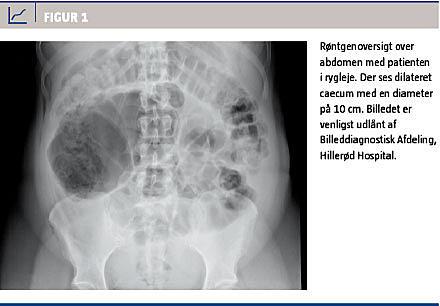

Diagnosen bygger på de kliniske og billeddiagnostiske fund sammenholdt med det forudgående forløb. En røntgenoversigt over abdomen (OOA) er den foretrukne undersøgelse (Figur 1) (evidens III) [7, 9]. OOA viser tarmdilatation, der involverer caecum og den proksimale colon, evt. hele colon [5, 10, 11]. Risikoen for perforation øges med stigende caecumdiameter (> 10-12 cm) og varighed af tilstanden (> 6 dage), (evidens IV) [4, 8, 12, 13]. I litteraturen er der ikke beskrevet tilfælde ved en perforation med caecumdiameter < 12 cm. Differentialdiagnostisk skal klinikeren udelukke mekanisk ileus, appendicitis, toksisk megacolon pga. Clostridium difficile-infektion, perforation, divertikulitis samt intra- eller retroperitoneal blødning [2, 13]. Hvis der ikke ses luft i hele colon inkl. rectum på OOA, foretages der computertomografi (CT) eller colonindhældning med vandopløselig kontrast for at udelukke mekanisk obstruktion.